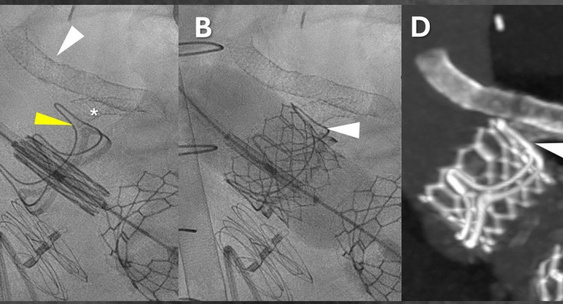

Американские врачи успешно провели первое в мире аортокоронарное шунтирование чрескожным доступом по бедренным сосудам без разрезов грудной клетки.N + 1

Вмешательство провели пациенту в тяжелом общем состоянии, чтобы избежать перекрытия устья левой коронарной артерии при замене протеза аортального клапана, в которой он нуждался.N + 1